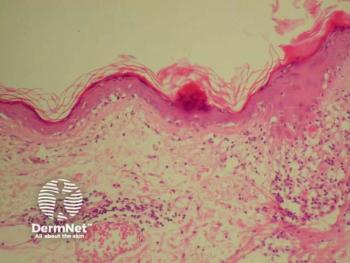

Expert tips from Whitney High, MD, at Elevate-Derm West 2024 guide experienced advanced practice providers in mastering dermatopathology and avoiding diagnostic pitfalls.